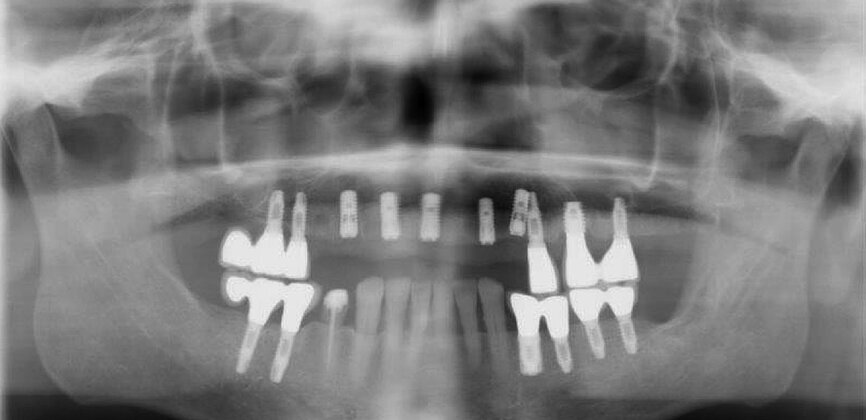

Fig. 14: Dental panoramic tomogram of initial situation.

The first was a 51-year-old patient who smoked 30 cigarettes per day and suffered from diabetes and stress (Figs. 1–8). The second was a 76-year-old male patient in good physical condition who smoked 40 cigarettes per day. He underwent reconstruction of the premaxilla (Figs. 9–13). The third was a healthy female patient of 24 years of age who smoked 20 cigarettes per day. She required a sinus lift in region #25 (Figs. 14–21). The patients were informed of the intended process in detail and signed the surgical protocol containing information concerning possible risks of failure and complications, as well as information on the alloplastic and synthetic materials to be used.

Digital radiographic images were taken at the time of surgery, 24 hours postoperatively and one month later in order to evaluate implant success (Figs. 6, 7, 11, 13, 15 & 20). In none of the patients inflammatory processes were found and all implants remained stable.